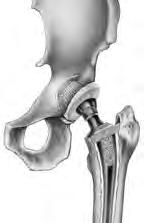

Total Hip Replacement

Total hip replacement (hip arthroplasty) is surgery to replace a hip joint damaged by wear, injury, or disease. The hip joint is a “ball and socket” joint and is your largest weight-bearing joint. The ball-shaped top of the femur (thighbone) sits in the acetabulum socket (hollow area) of the pelvic bone. The joint is held together by ligaments and muscles. The socket is lined with cartilage (firm, flexible tissue) that can become damaged or worn, causing pain. Arthritis, infection, injury, or loss of blood supply to the ball of the femur can damage the joint. You may need to have hip replacement surgery when you have unrelieved pain or problems with walking.

Your surgeon will make an incision (cut) on your hip. During the surgery your surgeon will access your hip joint by moving muscles and other structures to the side. The damaged parts of your hip joint will be removed using special tools. Implants made of metal, ceramic, and/or plastic will be fitted to replace the removed part of the bones. Your surgeon may then secure the implants using screws and cement, or create a tight fit if bone quality allows. Once in place, they are joined together just like a ball fitting in a socket, and the muscles and other tissues around the joint are moved back into their original positions. Your incision will be closed with stitches, staples, or glue and covered with a bandage. Having this surgery may ease your pain, make your hip joint more stable, and improve movement of your leg.

Hip Replacement Component